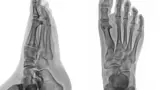

Digital X-RAY with High Definition Monitors

This modern technology is a giant leap from the conventional X-Ray films that would require development like old photography film.

Digital X-RAY provides instantaneous picture review with the ability to magnify suspected deformities. These X- Ray images are displayed in the patient exam rooms on 45” high definition monitors.

Copies of x-rays can be quickly copied on to a computer disk and sent with the patient or to other medical facilities.